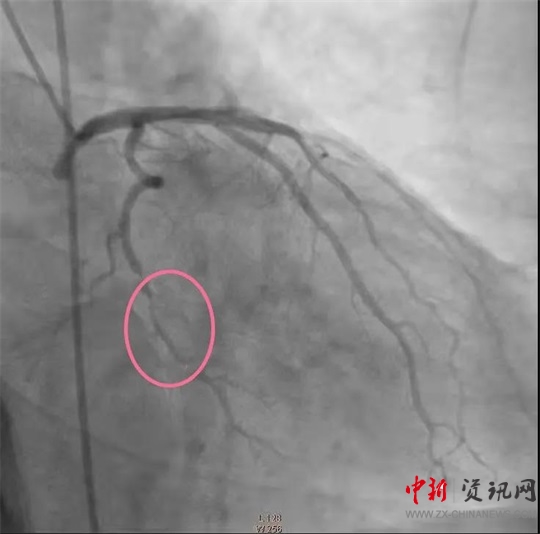

經(jīng)過一系列的術(shù)前準備并經(jīng)患者家屬同意后,立即繞行病房進入介入手術(shù)室,實施緊急手術(shù)。卒中中心團隊、胸痛中心團隊和介入團隊密切配合,為患者分別實施了腦動脈造影+主動脈弓造影+顱內(nèi)動脈瘤栓塞術(shù)+冠狀動脈造影術(shù)+經(jīng)皮冠狀動脈支架植入術(shù),成功把患者從死亡邊緣拉回。目前,患者病情穩(wěn)定,各項指標良好。

(冠脈支架植入前)